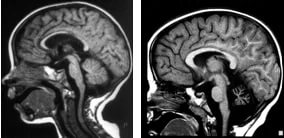

Мозжечковая дцп

Мозжечковая дцп 115 фото